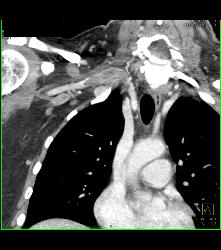

Cervical Rib With Occlusion of the Right Subclavian Artery- See Full Sequence